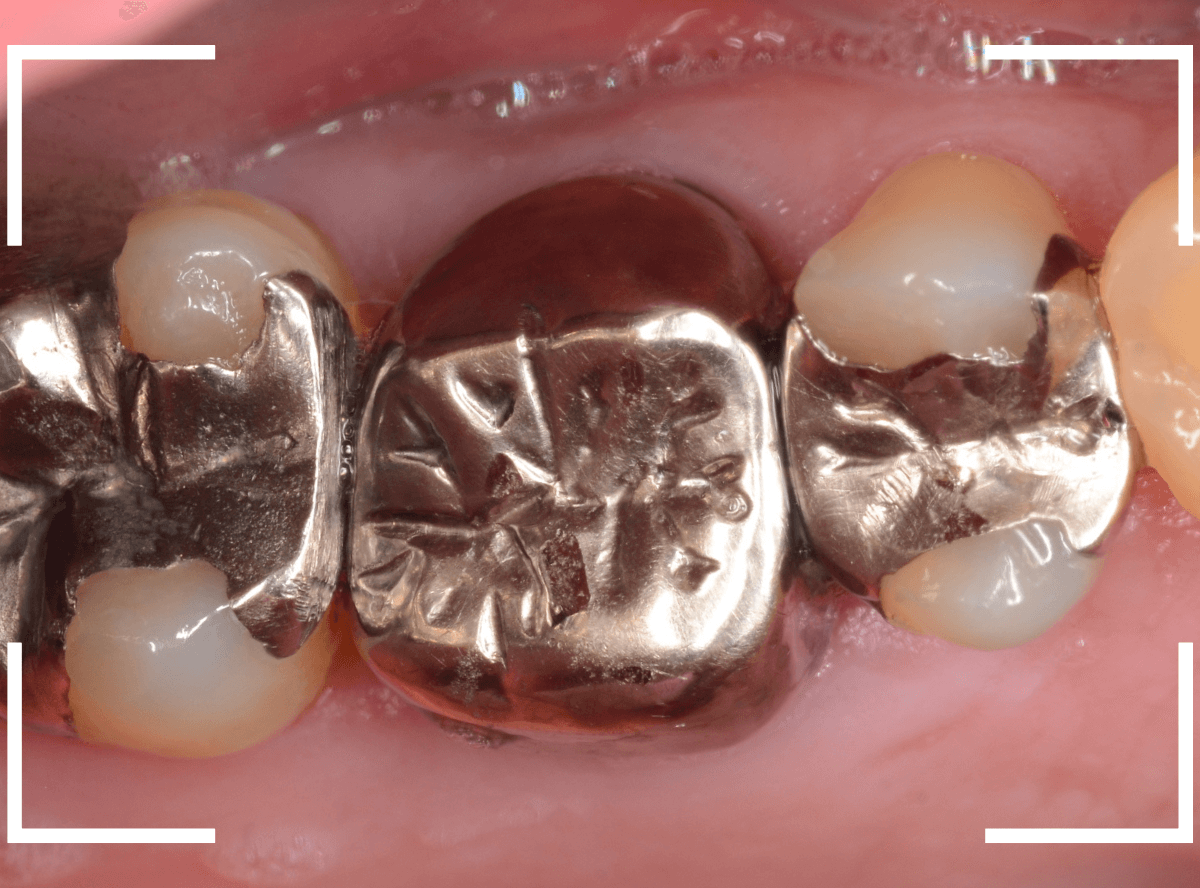

「下の奥歯の銀歯を白くしたい」というご希望の患者さんです。

メタル・インレーとメタル・クラウンが入っていますね。

検査の結果、再製に問題なさそうでしたので、治療を進める事になりました。

治療前後の写真になります。

やはり、印象が大きく変わりますね。